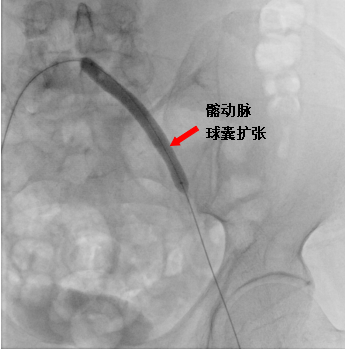

手术当天,易主任在病人左下肢动脉多处进行造影,考虑为血栓造成动脉闭塞,导管退至左侧髂外动脉起始部行溶栓治疗。

溶栓治疗后,后续又择期引入球囊导管,分别在左侧髂动脉、股浅动脉多处狭窄段进行球囊扩张,扩张后造影见血管扩张良好,血流通畅。